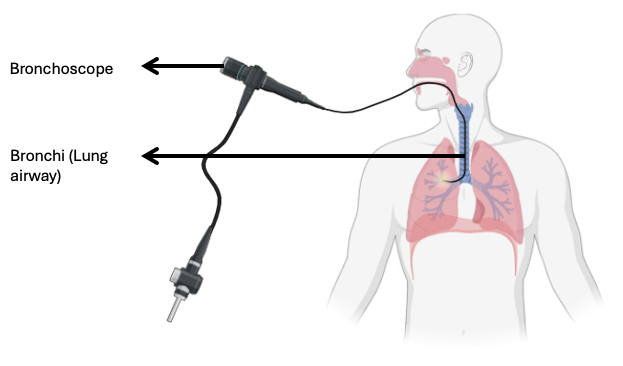

2 – Diagnostic Tools – Spirometry, Arterial Blood gas, Oximeter, Exercise Tolerance Testing, X-ray, Bronchoscopy, Culture and Sensitivity Tests, Sneezing Reflex, Coughing Reflex,